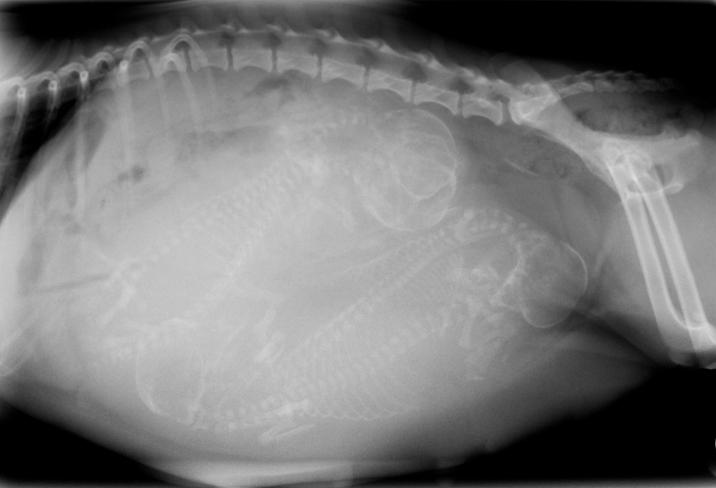

Antes de pasar a explicar si es normal que una perra sangre después del parto debemos saber qué le sucede a su cuerpo durante este período. El útero de la perra tiene forma de Y, con un cuerno uterino a cada lado, que es donde se van a alojar los cachorros. Por lo tanto, el primer cambio de consideración va a ser un aumento de tamaño del útero, que irá incrementándose paulatinamente según los cachorros van creciendo. Además, el útero va a concentrar una mayor cantidad de sangre para mantener a los fetos nutridos y asegurar su bienestar. Es por este motivo que una cirugía uterina, como puede ser una ovariohisterectomía si estamos ante una concepción no deseada o una cesárea si no es posible el parto natural, cuenta con el sangrado como una de las complicaciones a tener en cuenta.

Durante el parto, que tiene lugar aproximadamente a los 63 días de gestación, el útero se contrae para expulsar a los cachorros al exterior. Cada uno de ellos se encuentra envuelto en una bolsa llena de líquido amniótico y unido a la placenta mediante el cordón umbilical. Para nacer, la placenta se tiene que desprender del útero. En ocasiones, la bolsa se rompe antes de que el cachorro salga al exterior, pero es común que este nazca con la bolsa íntegra y será su madre quien la rompa con los dientes. También morderá el cordón umbilical y, de manera habitual, se comerá todos los restos.

- Subinvolución de los sitios de placentación: si observamos que los loquios se prolongan en el tiempo podríamos estar ante esta afección, que se produce porque el útero no puede completar su proceso de involución. La hemorragia, incluso no siendo muy abundante, puede provocar que nuestra perra tenga anemia. Puede diagnosticarse por palpación o ecografía.

- Metritis: se trata de una infección uterina que se puede producir por un ascenso de bacterias cuando el cuello del útero se encuentra abierto, por retención placentaria o momificación de algún feto. Los loquios van a tener muy mal olor y, además, la perra estará apagada, tendrá fiebre, no comerá ni se ocupará de los cachorros y pueden aparecer vómitos y diarrea. Se diagnostica por palpación o ecografía y requiere inmediata asistencia veterinaria.